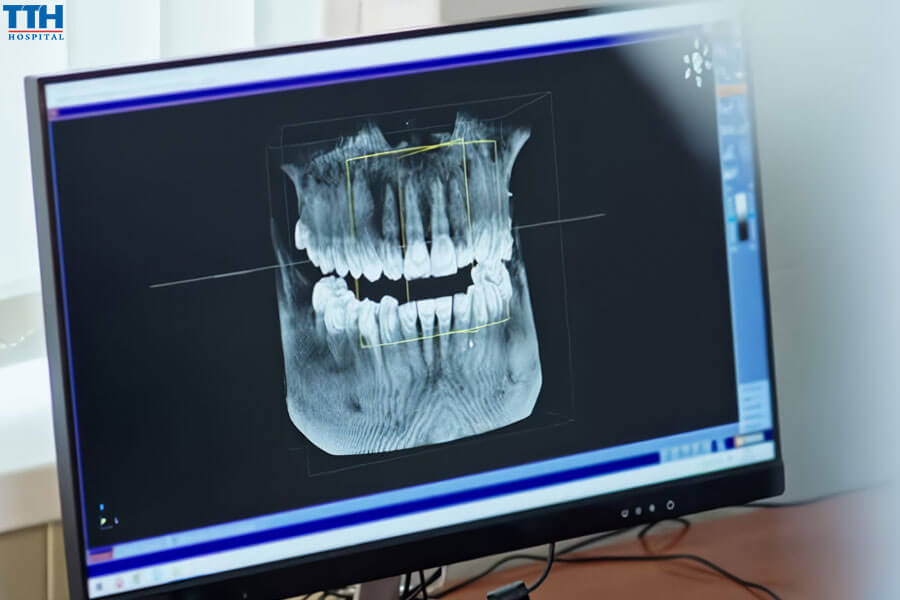

3.1. Các phương pháp đánh giá

- Chụp X-quang thông thường

- Chụp CT 3D (Cone Beam CT)

- Đánh giá mật độ xương

- Chụp X-quang và CT 3D